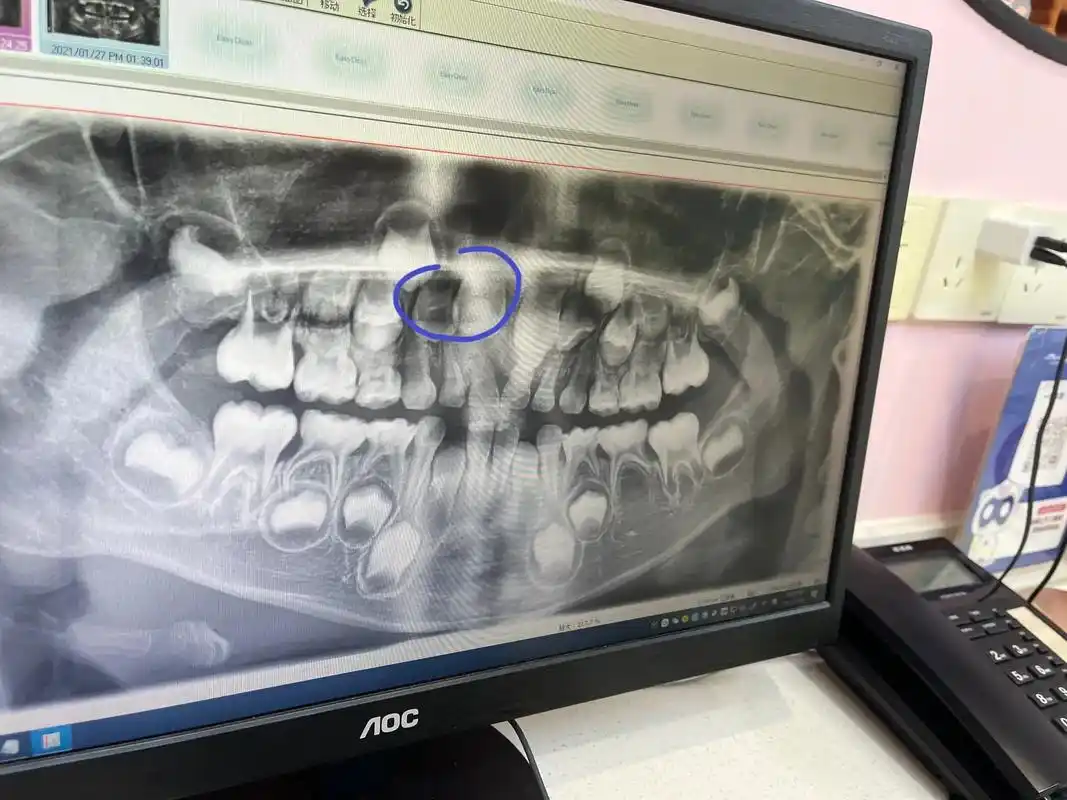

马嘉祺虎牙没了!牙套戴半年,限定"小钢牙"军训后摘掉

牙齿手术.#整牙历程 #牙齿矫正 #拔牙记 #掉牙的小孩 # - 抖音